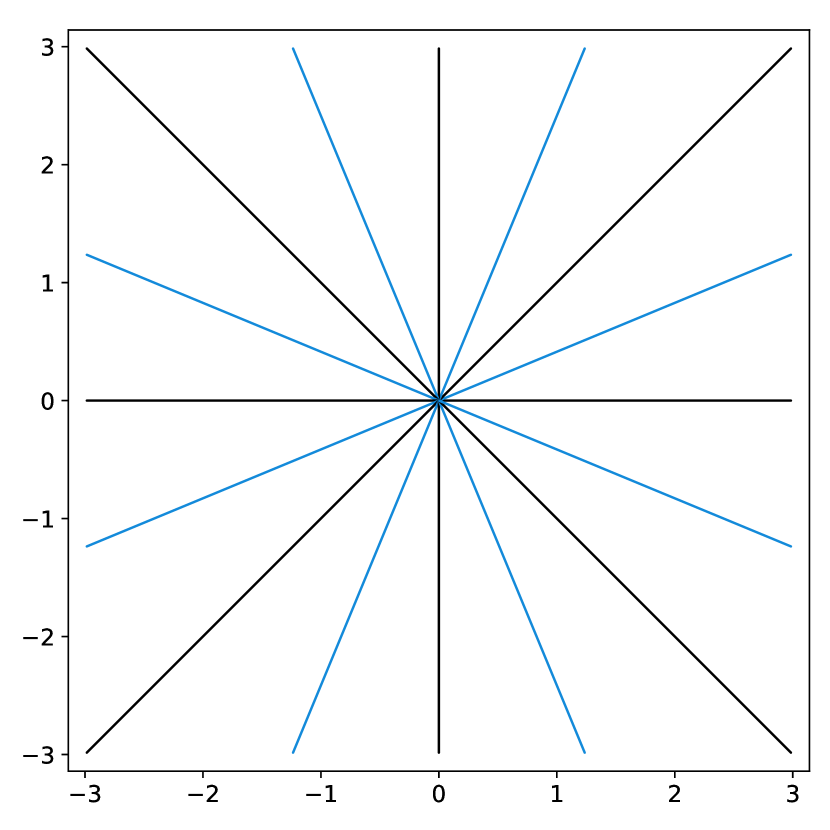

To illustrate this fact, we conducted a simple experiment in Fig. 1. Starting from two similar initial sampling trajectories, we let a multi-scale solver run for 14 epochs and 85 hours on the fastMRI knee database. We then evaluate the average reconstruction peak signal-to-noise ratio (PSNR) on the validation set. As can be seen, the final point configuration and the average performance varies by dB, which is significant. This suggests that the algorithm was trapped in a spurious local minimizer and illustrates the difficulty to globalize the convergence.

dB

dB